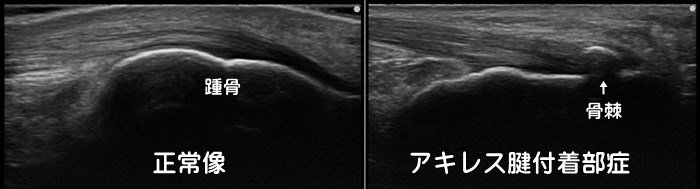

踵骨棘・アキレス腱付着部症

アキレス腱が踵の骨に付着する部分に繰り返すストレスがかかり続けると骨棘(こつきょく)と呼ばれる骨の増殖が見られます。アキレス腱付着部症では踵の骨の上を押すと痛みがあります。